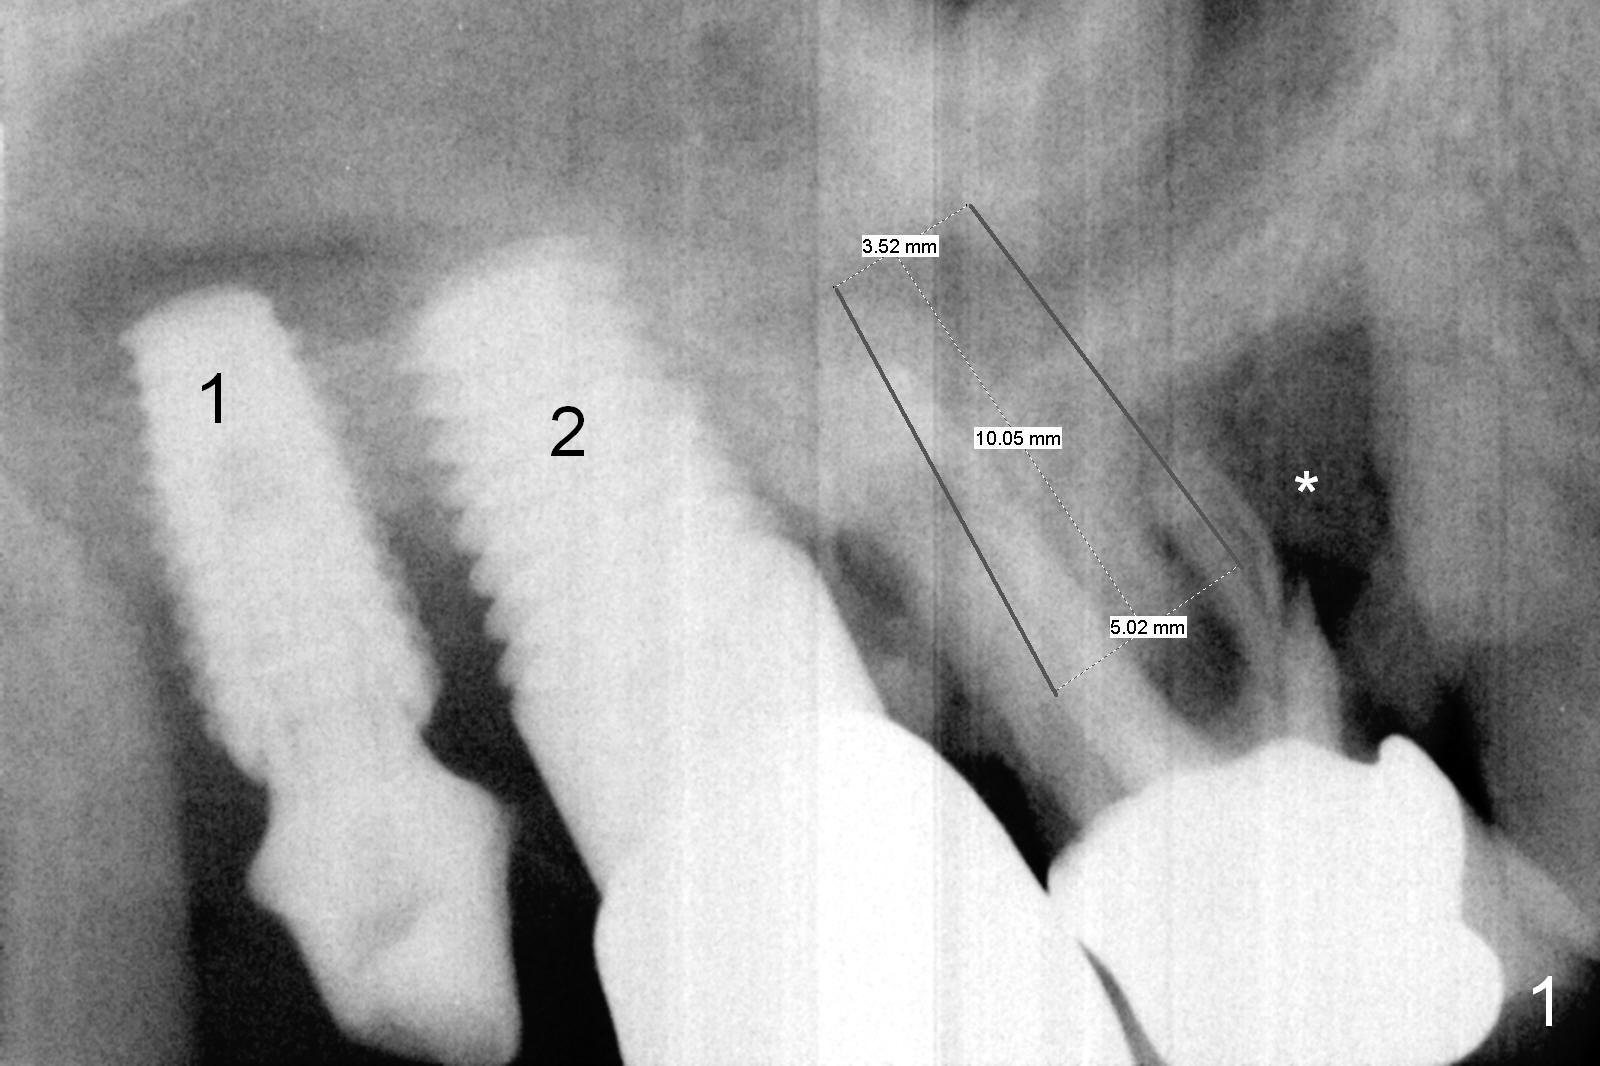

A 62-year-old man will return for #3 immediate implant, 2.5 years after #2 one and .5 year after #1 one (Fig.1).  It appears that the available bone for the implant is the septum, which is not large.   The implant is not expected to be large. Sinus lift is anticipated to obtain additional stability.  Prepare osteotomes and bone expander kit.  Since the bony defect is extensive (*), prepare more larger size of allograft than the small one and Osteogen.  The amount of graft should be large, looking at the socket after extraction.  The antibiotic will be Clindamycin.  Use amalgam carrier for sinus lift and larger one for the rest of grafting.  To keep the graft in place, try a large abutment, e.g., 7.5 mm.  If there is severe gingival recession, draw blood for PRF.  Take preop photos.